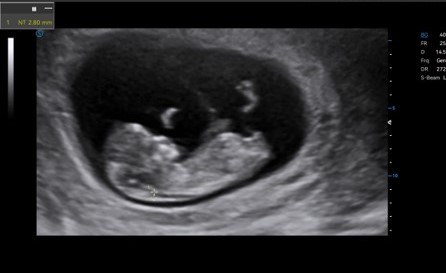

Auto NT automatically recognizes and measures the thickness of the fetal nuchal translucency.

Lumi 4D enables the adjustment of light source angle to support real-time static stereo imaging of the fetus.